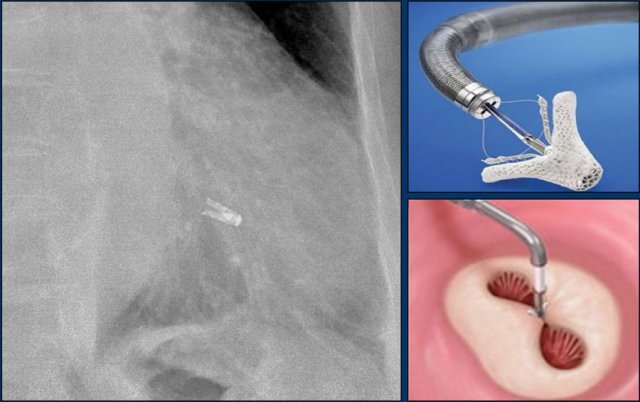

A Micra device is a small wireless pacemaker device, that is transfemorally implanted in the apex of the right ventricle.

Close up view of the Micra device.